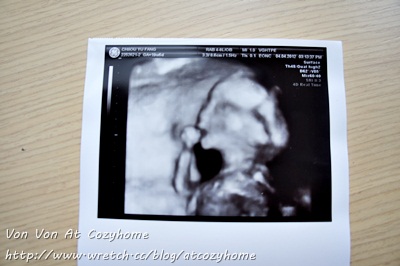

3/22(周四) 抵達台灣後的第二天我立刻前往振興醫院做產檢,台灣的超音波設備真的太先進了,讓我清楚地看見寶寶在我肚腹裡的樣子,他已經18週了,比美國醫生預估大一周,我很享受這一刻看見一個新生命正在我肚腹裡成長的幸福感。

原先我在美國中醫診所把脈時,中醫師斷言我這胎是個男孩,沒想到台灣產檢醫師看完超音波後說:『妳這胎是個妹妹耶! 而且長得很秀氣!』我聽到是 “妹妹” ,我驚喜地大叫起來,流著眼淚跟醫生說:『我真的太開心了!』醫生因我的反應嚇了一跳笑說:『生女孩有這麼開心嗎!』 我只能說醫生阿你不懂啦! 因為一直期待有女兒的我以為我這輩子應該是沒有女兒命了,沒想到今天來個大翻盤原來我這胎懷的是女兒,我怎能不開心。

產檢後,我難掩內心的喜悅一路臉上掛著笑容,我買了張HELLO KITTY的卡片夾著妹妹的超音波照片,將這個好消息寫在卡片上,想給今晚出差下飛機抵達台灣的KJ一個大大的驚喜! 相信KJ會跟我一樣開心的不得了!